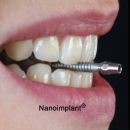

Tyto stránky prezentují Implantační systém Nanoimplant, kterým je možné řešit náhrady vlastních ztracených zubů titanovými zubními implantáty Nanoimplant. Informace jsou určeny pro veřejnost a zubní lékaře, kteří hodlají získat přehled o kvalitním českém implantačním systému z čistého nanostrukturního titanu. Nanostrukturní titan pro medicínské aplikace byl vyvinut ve spolupráci Timplant s.r.o. , USA (Los Alamos Laboratories) a Ruskem (Universitou pro letectví v Ufě). Dílčí výsledky vývoje jsou popsány v článcích - viz kap. PUBLIKACE

- Implantační systém Nanoimplant - první na světě vyroben z nanostrukturního titanu

Video Nanoimplant® - Dentální implantační systém

Připravili jsme si pro vás video dentálního implantačního systému Nanoimplant. První dentální implantát z nanostrukturního..